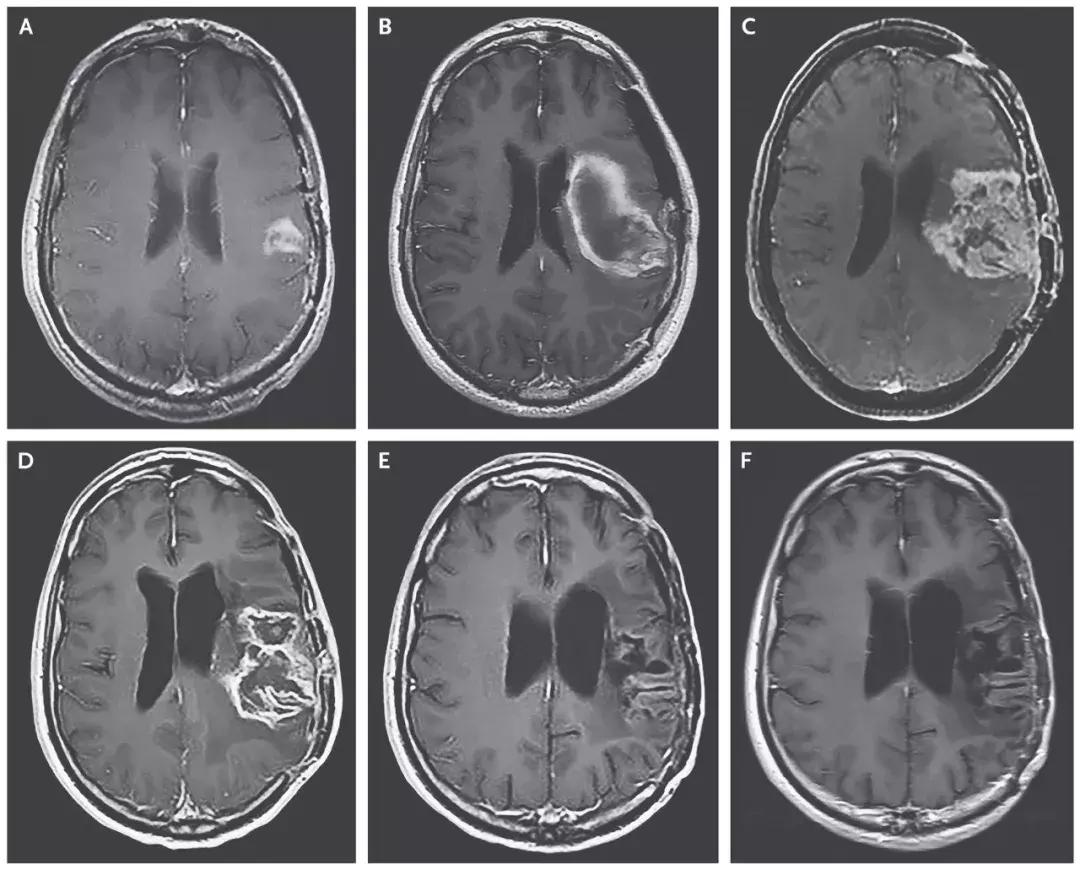

近日,美国杜克大学癌症研究所的科学家们使用脊髓灰质炎病毒(PVSRIPO),显著延长了脑胶质母细胞瘤患者的生命的重磅研究发表在顶尖医学期刊《新英格兰医学杂志》(NEJM)上的研究引起医学界广泛关注。

研究人员在一项1期临床试验中,总共招募了61名患者,并在他们的头骨上设置了导管,让病毒得以直接进入大脑,攻击肿瘤。CD155在胶质母细胞瘤中有高度表达,而这种经过处理的病毒能针对表达CD155的肿瘤细胞,选择性地入侵并进行复制,最终导致肿瘤细胞的裂解。

试验结果

- 治疗组的中位生存期是12.5个月,与11.3个月的历史数据相差无几;

- 在2年这个时间节点上,治疗组的生存率是21%,已经比历史数据(14%)高出50%;

- 在3年这个节点,治疗组的生存率同样为21%,而历史数据仅为4%。这意味,经过病毒的治疗后,这个生存率猛增5倍!

溶瘤病毒创造恶性脑瘤完全缓解的治疗奇迹!

截止2018年3月20日,8名患者对治疗产生治疗应答,2名患者的脑胶质瘤病灶完全消失,达到了完全缓解!

▲患者脑部肿瘤的缩小清晰可见(图片来源:《NEJM》)

这位患者,经过PVSRIPO溶瘤病毒治疗7个月后,病情复发后使用洛莫司汀治疗,经过12个月的洛莫司汀治疗后,病人的病灶完全消失并保持了20个月的无病状态,并且在PVSRIPO溶瘤病毒治疗发生出血后57.5个月仍然存活。